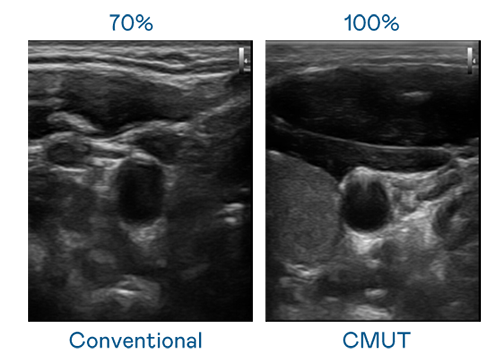

CMUT 技术是一种用电容式微机电元件来产生超音波讯号的技术。与传统 PZT 压电式技术相比,CMUT 频宽增加 30%,更宽频的超音波讯号让影像解析度大幅提升,是实现高影像品质医疗超音波扫描、促进精准医疗发展的关键技术。

超音波影像的解析度高低,首先取决于探头能发出的讯号频宽。拉斯维加斯 CMUT 可提供高清晰的超音波讯号,提供高频宽、高灵敏度、影像纹理细节更高的超音波影像,协助医护人员缩短影像判读时间及利用精准的医疗影像进行诊断。